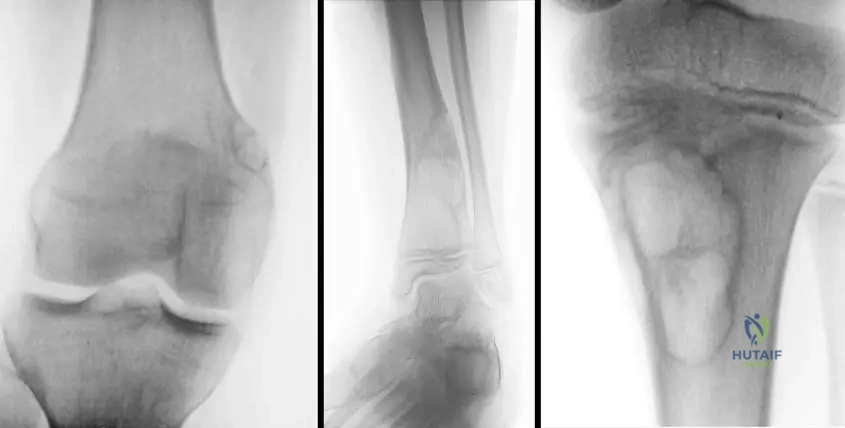

A 12-year-old male presents for evaluation of knee pain following a minor fall. Radiographs of the knee are obtained, revealing an incidental, sharply marginated, eccentric, metaphyseal lesion in the distal femur. He denies any prior symptoms related to this area. Physical examination is unremarkable. What is the most likely diagnosis?

View Answer & Explanation

Correct Answer: C

Rationale: Nonossifying fibromas (metaphyseal fibrous defects) are commonly detected incidentally in the second decade, are eccentric and metaphyseal, often in the distal femur, and are sharply marginated. The patient's age, incidental finding, and radiographic characteristics are classic for a nonossifying fibroma. Osteosarcoma would typically present with pain, a more aggressive appearance, and often nuclear atypia on histology. Enchondroma is typically diaphyseal or metaphyseal but often central, and less common in the distal femur as an incidental finding with these specific features. Osteoid osteoma presents with characteristic nocturnal pain relieved by NSAIDs and a nidus. Fibrous dysplasia can be metaphyseal but often has a "ground glass" appearance and is less commonly sharply marginated in this context.

A 16-year-old male presents to the emergency department after sustaining a fall during a basketball game, resulting in a pathologic fracture through a large lesion in his distal femur. Radiographs show an eccentric, metaphyseal lesion with cortical thinning, occupying more than 60% of the bone diameter. Physical examination reveals local tenderness over the fracture site. What is the most likely underlying lesion?

Correct Answer: B

Rationale: The clinical scenario describes a patient in the second decade with a large, eccentric, metaphyseal lesion in the distal femur that has resulted in a pathologic fracture. The text explicitly states that "For large lesions occupying more than half of the bone diameter, patients may present with a pathologic fracture and have local tenderness," which is characteristic of a nonossifying fibroma. Osteochondroma is an exostosis and typically does not cause pathologic fractures through the bone shaft. Chondrosarcoma and Ewing sarcoma are malignant tumors with different typical presentations and radiographic features. Simple bone cysts are typically central and often in the proximal humerus or femur, and while they can fracture, the eccentric and lobular description points more towards NOF.

A 15-year-old male presents with an incidental finding of a nonossifying fibroma in the proximal tibia. Radiographs demonstrate a sharply marginated lesion. What is the typical location of these lesions within the long bones?

Rationale: The text explicitly states, "These lesions are usually eccentric and metaphyseal." The image captions also reinforce this, showing lesions in the distal femur, distal tibia, and proximal tibia, all metaphyseal regions. Diaphyseal, epiphyseal, articular, or purely cortical locations are not the typical presentation described.